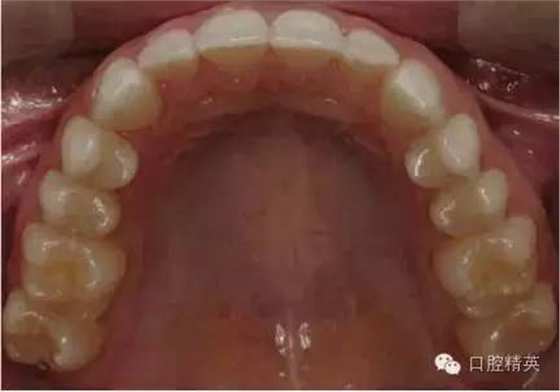

上颌合面照

合面观

1:2 (1:3)放大倍率

需要使用拉钩及反光板

•合面照需要使用成像清晰的反光镜。

•请拍摄时使用拉钩,否则软组织会包裹镜面阻挡牙面。

•中切牙唇面应位于相片边缘处。

•取景时应尽量减少反光镜边缘和嘴唇的暴露。患者的鼻子或非反光成像的牙齿应不要位于画面中。

•轻吹反光镜或将反光镜泡于温水中能减少镜面雾气的形成。

•相机应位于反光镜镜面45°左右处。反光镜中的成像应为牙齿的舌侧及唇侧都可见。一个过浅的拍照角会使得唇颊面及舌腭面的楔状隙角度记录有误。

•尽量暴露所有的牙齿。至少应包括从中切牙到第二磨牙近中。前牙应始终能清晰成像。

•照片中应能清晰显示上切牙边缘位置、唇颊侧及舌腭侧楔状隙。

•此照片可以从患者正前方拍摄(镜头稍向上斜),或可以直接位于病人后方而病人斜靠椅背。

•焦点位于反光镜中的双尖牙。

•开始先使用1:2 (1:3)放大倍率,然后调整放大倍率以拍摄上颌牙弓。